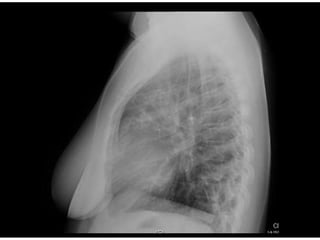

Este documento presenta el caso de una mujer de 28 años de Guinea Ecuatorial que consulta por tos de un mes de evolución. La exploración física muestra crepitantes en ambos campos pulmonares. Las pruebas complementarias revelan anemia microcítica y una PCR elevada. Las serologías son negativas para VIH y VHC pero positivas para anticuerpos de citomegalovirus y del núcleo del virus de la hepatitis B.